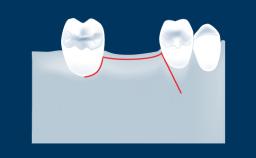

O tratamento com implantes dentais requer um procedimento cirúrgico para a instalação do implante e muitas vezes envolve procedimentos cirúrgicos adicionais, como extração dentária e aumento ósseo. Cada procedimento cria uma ferida. Para uma cicatrização ideal, os retalhos cirúrgicos - e muitas vezes outras feridas cirúrgicas - devem ser adequadamente fechados com suturas. O fechamento satisfatório de feridas e retalhos cirúrgicos promove a cicatrização e reduz complicações como abertura da ferida, deiscência e infecção. Este módulo apresentará os materiais e as técnicas apropriadas para sutura que contribuem para um resultado bem-sucedido, bem como técnicas inadequadas que podem levar a possíveis complicações.